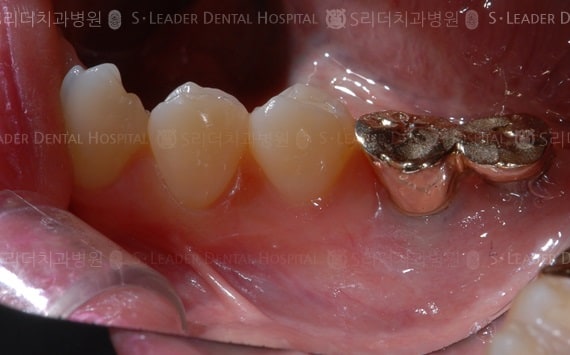

20140425050415_1_923152.JPG 20140425050415_2_522570.JPG

틀니임플란트,부분틀니,15년 10개월 경과